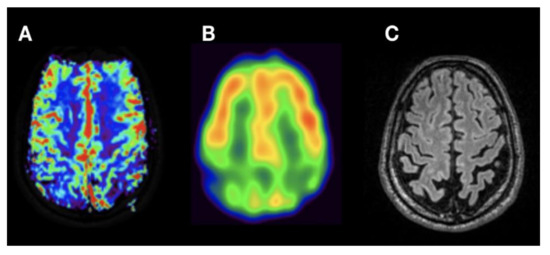

3. Results